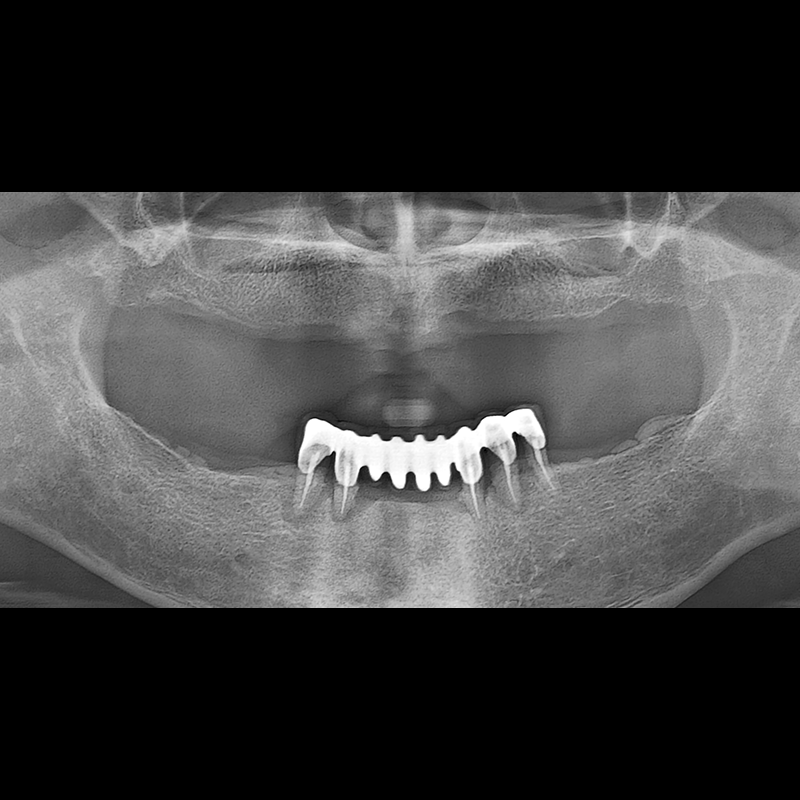

BEFORE AFTER

种植牙前后的照片 2025.05.30

在缺失的牙齿部分和难以挽救的牙齿位置植入了种植牙。